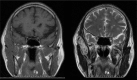

Diagnoses: Computed tomography (CT) scan showed the lesion across the zygomatic arch, with many calcified nodules differ in sizes and no erosion to the bone, magnetic resonance imaging (MRI) showed an oval lesion with hypointense and isointense on T2-weighted imaging within the temporal muscle, and preoperation diagnosis was hemangioma.